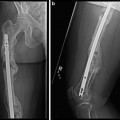

Fig. 2

(a and b): Immediate post-operative radiographs after resection of comminuted and devitalized bones (square osteotomy of bone ends) and application of Ilizarov external fixator and proximal tibial Gigli saw osteotomy for bone transport